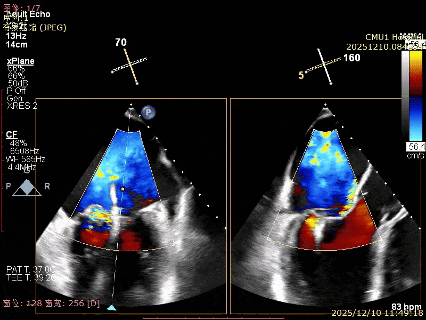

患者食道胃底静脉曲张,遂行TTE术前评估

术前TTE评估:

MR反流病因:DMR(部分腱索断裂)、Carpentier II型;

反流程度:极重度(5+),PISA法估测EROA约1.12cm²,R-VOL约98ml;

病变情况:P2-部分P3,脱垂宽度约27mm ,连枷间距11-13mm,瓣口面积7.8cm²,PML约25mm

其他:TR(重度) ,间接估测PASP约65mmHg;

预估手术难点:后叶冗长,脱垂宽度大,连枷间距大。

为了避免长时间TEE对食道造成损伤,术前即刻3D-TEE短时进一步明确二尖瓣病变相关解剖情况。

术前3Dcolor

3D-TEE二尖瓣相关解剖学参数:后叶长度:22-25mm,前叶长度:31-34mm;瓣环AP径:47mm,ML径:48mm;瓣口面积:约7.8cm²;脱垂宽度:30mm,最大连枷间距:14mm。

四条肺静脉均可测及收缩期反向血流

术前即刻TEE进一步明确了二尖瓣反流的机制(DMR)及反流程度(5+),重点完善了病变区域二尖瓣解剖结构的评估,预估手术难点/影响手术效果的解剖结构为冗长的二尖瓣后叶(PML约25mm),宽大的脱垂(Flail Width约30mm),超大的连枷间距(Flail gap约14mm)。